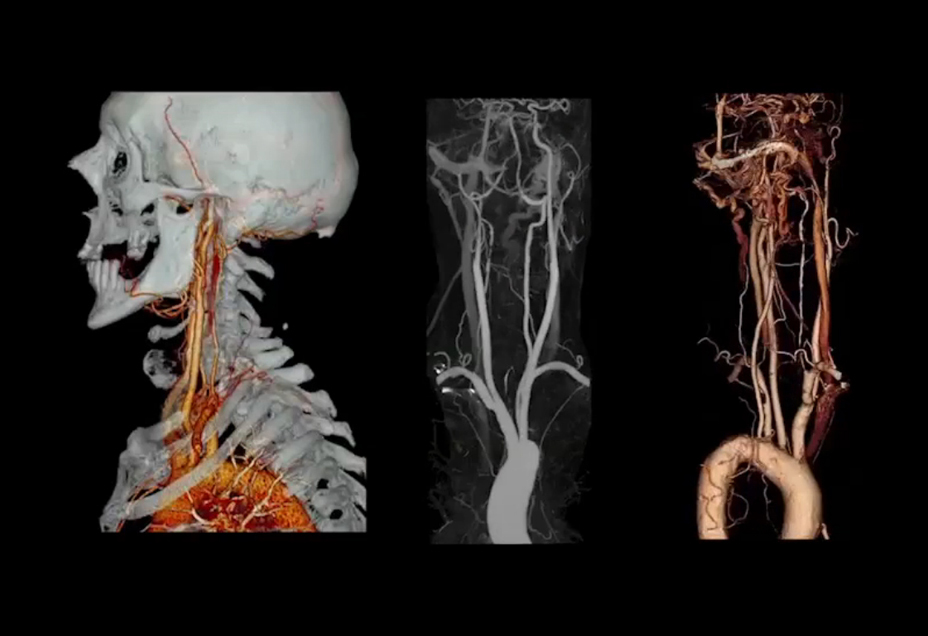

SURESubtraction ™ обладает способностью удалять кости и кальций из наборов данных, позволяя клиницистам видеть опухоли или артерии в группе риска. В настоящее время доступны для изучения мозга, каротидных, ортопедических и легких.

Используя полностью автоматизированный нежесткий алгоритм регистрации Toshiba, вычитание костной ткани, кальция и стента может быть выполнено с помощью сканирования с низкой дозой без увеличения контраста до доставки контраста. Вы можете видеть превосходную визуализацию позвоночных артерий и внутренних сонных артерий, экономя время и улучшая диагностическую точность.

Вычитание CTA

Превосходная визуализация в КТс истинным вычитанием кости и кальцификацией.